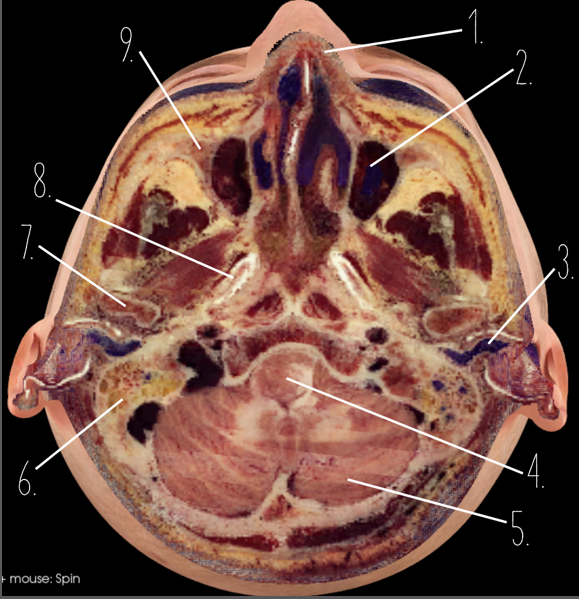

1?

Hard Palate

2?

Maxillary Bone

3?

Mandibular Rami

4?

Dens

5?

Transverse Foramen C1

6?

Spinal Cord

7?

Auricle

8?

Atlas